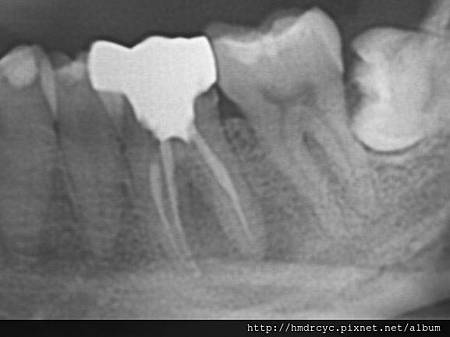

假牙必須利用X光片來更精確的判斷有沒有問題

在X光上面假牙是白色的影像

但X光片判讀困難 所以這部分必須仰賴醫師的專業

1. 蛀牙

蛀牙是常見的問題

X光上則是一個黑色的蛀洞可以參考蛀牙範圍

X光通常會有1-2mm的誤差

所以實際上牙齒裡的洞會比影像大

只要牙套底下出現X光可以辨別的蛀洞

未來繼續蛀牙的速度會很快

牙套內的牙齒也會流失的很嚴重